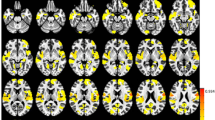

Compared to the PD-IC group, the PD-MCI-LD group exhibited decreased rsFC in a few small areas involving the right inferior orbitofrontal and right inferior temporal gyri while no significantly increased rsFC was observed. On the other hand, the PD-MCI-SD group exhibited substantial altered rsFC relative to the PD-IC group with decreased rsFC being observed in the bilateral frontal areas; meanwhile, increased rsFC was observed in the bilateral parietal and occipital areas (Fig. 2 and Supplementary Table 1). Increased rsFC in the posterior cortical areas was attributable to loss of anti-correlation, while decreased rsFC in the frontal areas was attributable to declined positive correlation noted in the PD-IC group (Supplementary Figure 1).

Group comparisons of rsFC using the bilateral SI as the seed in all group contrasts. Abbreviations: PD-MCI-SD = Parkinson’s disease with a shorter duration of parkinsonism before mild cognitive impairment diagnosis; PD-MCI-LD = Parkinson’s disease with a longer duration of parkinsonism before mild cognitive impairment diagnosis; PD-IC = Parkinson’s disease with intact cognition; rsFC = resting-state functional connectivity; SI = Substantia innominata.

When the PD-MCI-SD and PD-MCI-LD groups were directly compared, the PD-MCI-SD group showed decreased rsFC in the bilateral frontal and parietal areas including the precuneus, while increased functional connectivity was observed in the right primary somatosensory area (Fig. 2 and Supplementary Table 1). Significant group differences in the bilateral parietal areas and precuneus were attributable to the opposite direction of rsFC with the bilateral SI seed between the PD-MCI groups: positive correlation in the PD-MCI-LD group and negative correlation in the PD-MCI-SD group. On the other hand, decreased rsFC in the bilateral frontal areas was due to prominent anti-correlation between the bilateral SI seed in the PD-MCI-SD group (Supplementary Figure 2).